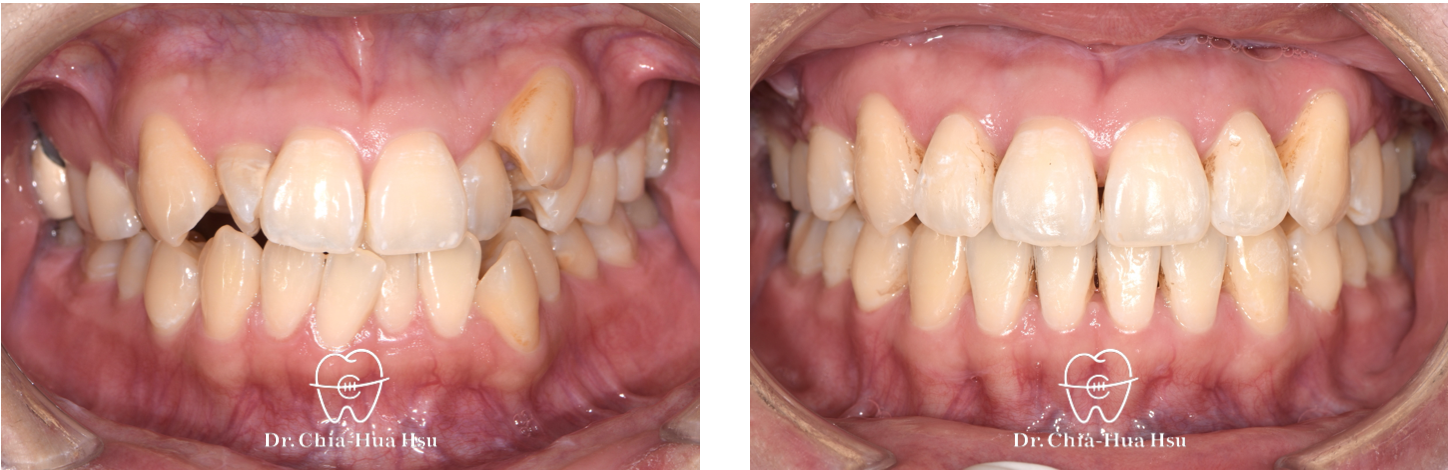

治療前

治療後